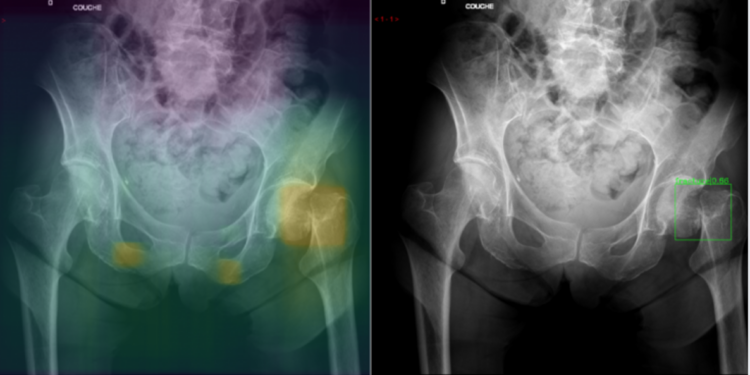

Au Maroc, l’IA est utilisée dans plusieurs domaines, tels que l’oncologie (cancers du sein et de la prostate), l’orthopédie (fractures), la neurologie (maladie d’Alzheimer) et l’hépatologie (transplantations hépatiques). Cependant, ces technologies ne sont pas encore accessibles partout. Elles se trouvent principalement dans les grands centres médicaux spécialisés, où la demande est plus importante.